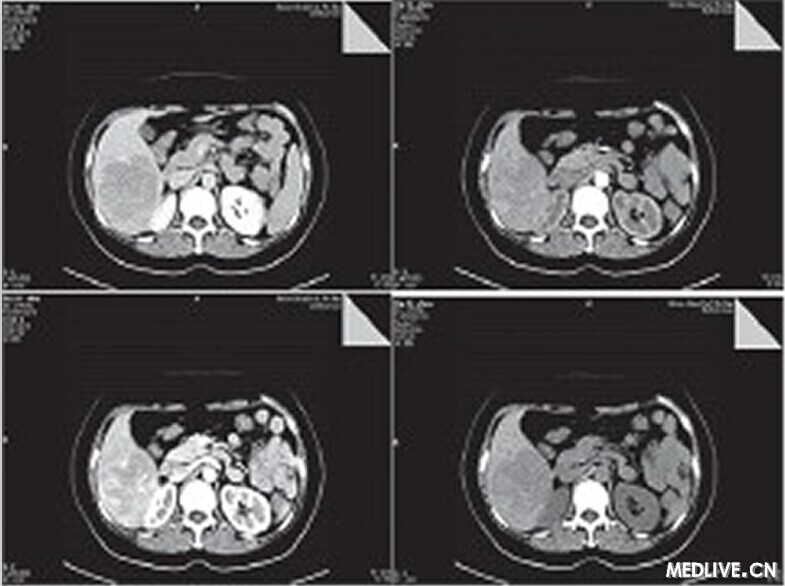

• 【PHILIPS每日一例】【誤診分析】肝臟血管平滑肌脂肪瘤誤診為肝癌一例

【PHILIPS每日一例】【誤診分析】肝臟血管平滑肌脂肪瘤誤診為肝癌一例

患者,女,50歲,農(nóng)民。

因右上腹疼痛1月余,外院B超診斷為肝癌入我院治療。既往無肝炎病史,無飲酒史,無遺傳病史,無高血壓糖尿病史。

體檢:神志清楚,正力體型,皮膚鞏膜無黃染;心肺聽診未見異常;腹軟,肝脾肋下未及,腹水征陰性,雙下肢無水腫。

入院后輔助檢查:甲胎蛋白正常,肝功能正常,血常規(guī)正常,便常規(guī)見膿球1~3個,HBV和HCV相關(guān)病原學(xué)檢查陰性。

CT檢